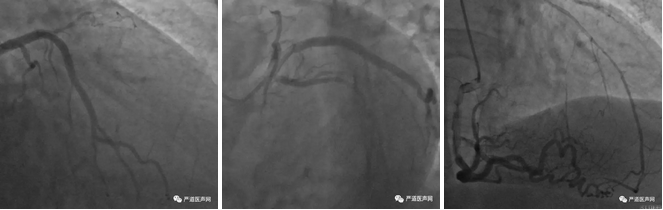

1周前外院造影显示:RCA,LCX,LM大致正常,LAD齐头闭塞,逆向侧枝分别为:

1. 经穿隔支提供自身逆向侧枝(迂曲度大);

2.经RCA-右室支-心外膜侧枝提供逆向侧枝(迂曲度大);

3. RCA-PD分支经间隔支提供逆向侧枝(CC-2级及CC-0-1级)。

4. 经RCA-右室支-间隔支提供逆向侧枝(z字形扭曲)。CTO远端终止于LAD-D分叉处。

此次手术首先进行了双侧造影,正向使用的是经股动脉7F EBU3.5的指引导管,逆向是经桡动脉6F AL1.0导管。多个体位双侧造影结果可见右冠优势型,右冠发出数条侧支血管为闭塞的前降支提供血流灌注,包括右室后支、及后降支等。其中右室支较为粗大,但是走行迂曲,通过心外膜经心尖为前降支逆向供血,此外后降支也同样有可供逆向操作的侧支血管。前降支的闭塞病变为齐头无残端的闭塞,长度约20mm,入口处有钙化。因此J-CTO评分3分。